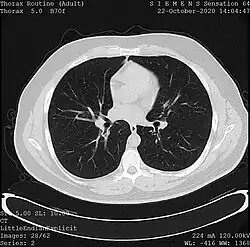

One frame of a CT scan of the chest showing the heart and lungs

• X-ray computed tomography (CT), or Computed Axial Tomography (CAT) scan, is a helical tomography technique (latest generation), which traditionally produces a 2D image of the structures in a thin section of the body. In CT, a beam of X-rays spins around an object being examined and is picked up by sensitive radiation detectors after having penetrated the object from multiple angles. A computer then analyses the information received from the scanner's detectors and constructs a detailed image of the object and its contents using the mathematical principles laid out in the Radon transform. It has a greater ionizing radiation dose burden than projection radiography; repeated scans must be limited to avoid health effects. CT is based on the same principles as X-ray projections but in this case, the patient is enclosed in a surrounding ring of detectors assigned with 500–1000 scintillation detectors[20] (fourth-generation X-ray CT scanner geometry). Previously in older generation scanners, the X-ray beam was paired by a translating source and detector. Computed tomography has almost completely replaced focal plane tomography in X-ray tomography imaging.